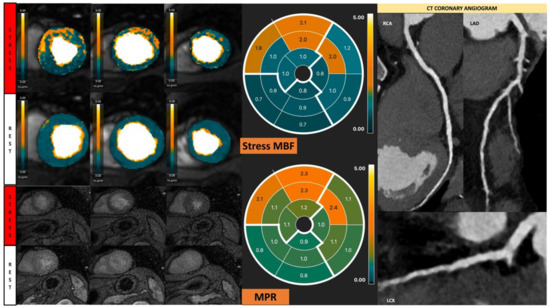

Visual assessment is subjective and highly dependent on expertise. Semi-quantitative and fully quantitative analysis of CMR perfusion based on signal intensity (SI) curves during the first pass of gadolinium contrast are solutions to this issue (Figure 5) [24]. Analysis methods that describe characteristics of the SI profile without estimating myocardial blood flow (MBF) are typically referred to as semi-quantitative analysis. The parameter calculated has been given various terms, such as the myocardial perfusion reserve (MPR) or the myocardial perfusion reserve index (MPRI) [20]. The calculation of these parameters has varied over time. For simplicity, we will refer to this as MPR, which is calculated as the ratio of MBF at peak stress and rest [25]. The MPR assesses the vasodilatory capability in response to vasodilator stress [26]. However, the MPR calculation and technique can result in different MPR values across scanners depending on how accurately the arterial input function (AIF) has been accounted for [27]. The accurate measurement of the arterial input function is an important requirement to quantify actual myocardial blood flow. To overcome the saturation or blunting of T1 signal intensity that prevents the precise measurement of the AIF, two methods have been utilised. One is a dual-bolus method [26], and the other is a dual-sequence technique [27].

Figure 5.

Contoured perfusion image (left) and signal intensity graph (right). Left panel demonstrates the contouring of right ventricle (yellow circle) and epicardium (green circle) and subendocardium (red circle) of left ventricle. Right panel shows the signal profile of each segment and blood pool.